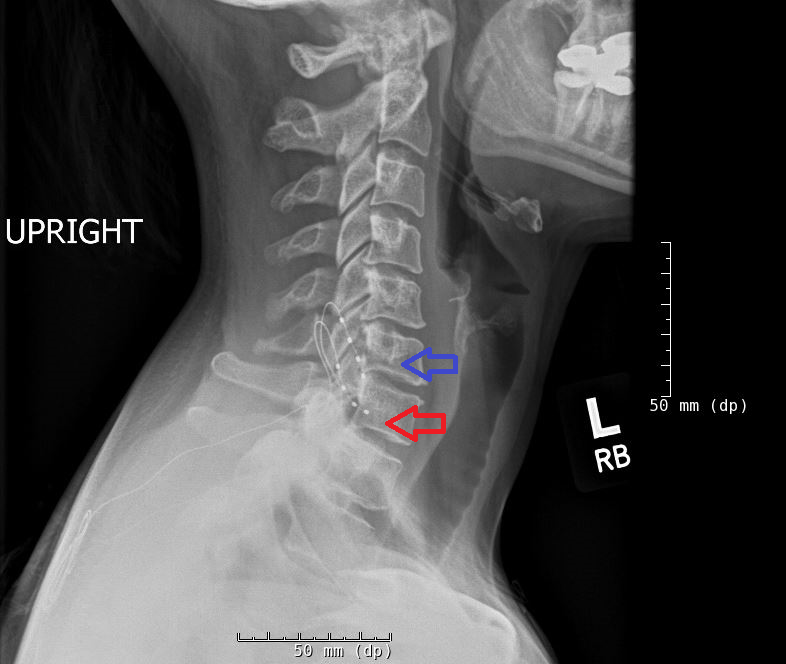

Dorsal root ganglion stimulation (DRGS) has emerged as an important refinement and advancement in the application of neuromodulation therapy for pain management, demonstrating efficacy in several chronic pain conditions as well as a variety of anatomic locations. DRGS employs a smaller diameter electrode than conventional spinal cord stimulation (cSCS), positioned along the peripheral nerve root where the sensory fibers are discretely separated from the motor fibers. Consequently, DRGS improves upon certain shortcomings encountered with cSCS such as positional-related changes in stimulation efficacy and paresthesia, difficulty in coverage of certain body parts such as the foot and pelvic region, paresthesias in unwanted areas, and decreased pain relief over time.